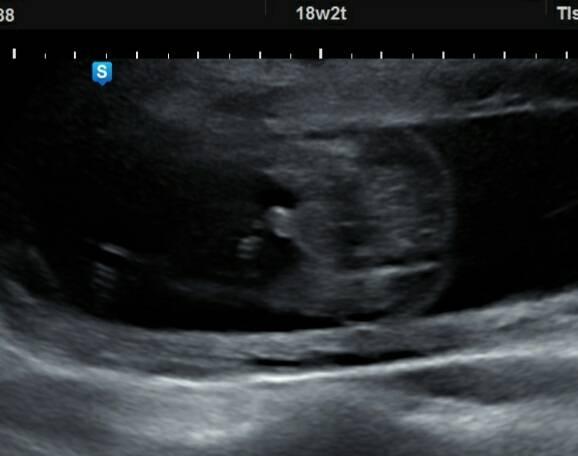

Hatte heute meinen zweiten großen Ultraschall. Baby wiegt 250g und alle Organe sind unauffällig. Und nach langer Geduld hat es sich tatsächlich kurz gezeigt und wir sind im Team ... unser Sohn bekommt einen kleinen Bruder

Bin heute bei 18+2. In der 14. Ssw kann man da doch noch gar nix sehen, nicht mal erahnen. Meine FÄ meinte in der 15. Ssw dass man da nix erkennen kann, alles noch so klein und wenn es ein Mädchen wäre, könnte sie es erst recht nicht sehen... ich drück dir die Daumen, dass es ein Mädchen ist. Wir hätten auch gern ein Mädchen gehabt, aber wir sind einfach froh und dankbar, dass alles gut ist und der kleine Mann gesund ist!

Bin in der 19.ssw. wir dachten eigentlich nicht, dass es sich zeigt, es hatte nämlich immer die beine zusammengekniffen. Aber meine FÄ wollte es auch unbedingt wissen und nach fast 20 Minuten, hat es kurz die beinchen geöffnet.... hier das eindeutige bildchen